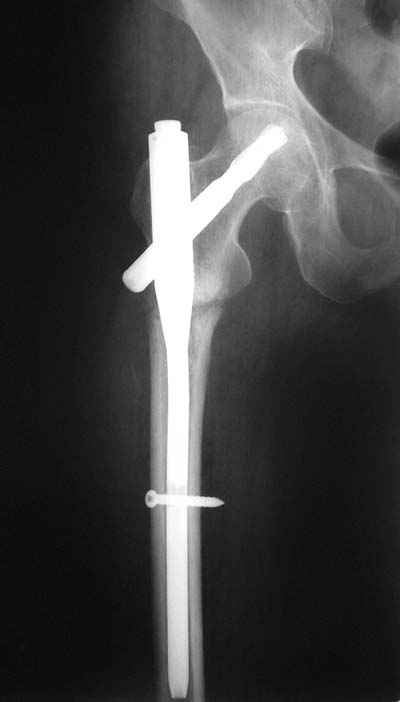

Да? Качество рентгенограмм конечно неочень, но ведь это нестабильный перелом 31.А2.2, не так ли?

Не думаю так. см вложение.

> Да? Качество рентгенограмм конечно неочень, но ведь это

Ну, после помещения туда такого гвоздя даже без дистального винта заметной нестабильности уже не остается ;-)

Для такого перелома вполне может быть использован диафизарный штифт, который отечественного производства я даже боюсь считать во сколько раз дешевле... Недавно несколько примеров я закидывал.